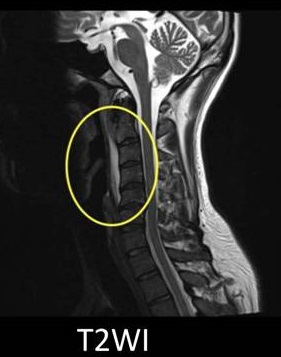

頚長筋 石灰化 (484 無料写真)

石灰沈着性頸長筋腱炎関節痛・筋肉痛と内科の病気 - みやけ内科・循環器科 総合内科のアプローチ。